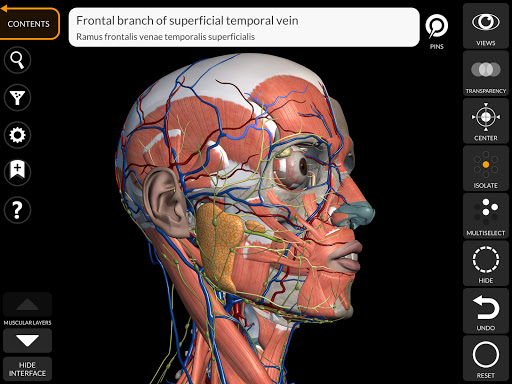

"Anatomy 3D Atlas" vous permet d'étudier l'anatomie humaine de manière simple et interactive.

Grâce à une interface simple et intuitive, il est possible d'observer chaque structure anatomique sous n'importe quel angle.

Les modèles anatomiques 3D sont particulièrement détaillés et avec des textures jusqu'à une résolution de 4k.

• Visualisation des muscles à travers des niveaux de couches depuis les plus superficielles jusqu'aux plus profondes

• En sélectionnant un modèle ou une épingle, le terme anatomique associé apparaît

• Description des muscles : origine, insertion, innervation et action